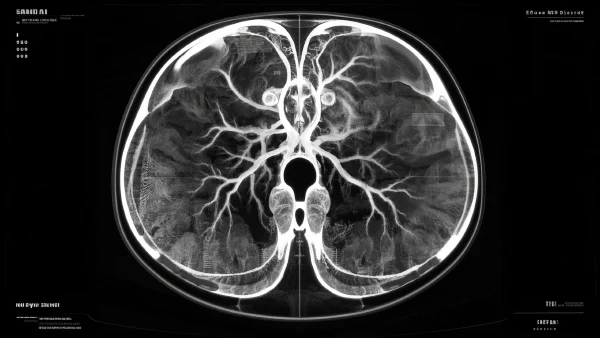

医生在超声、CT或MRI上最主要关注血管分布。动静脉畸形常见的影像表现是:一团团不规则的管道混杂,没有正常的毛细血管“过滤带”,动脉血直接蹿进静脉,就像水龙头直接连着下水管。

影像上还会看到瘤样扩张、异常血流速度等细节。这些特征决定后续处理方式——比如如果影像发现畸形正好压迫神经,方案就会偏向干预治疗。也有患者因为影像上血管非常复杂,医生更倾向于使用多学科会诊讨论最安全路线。